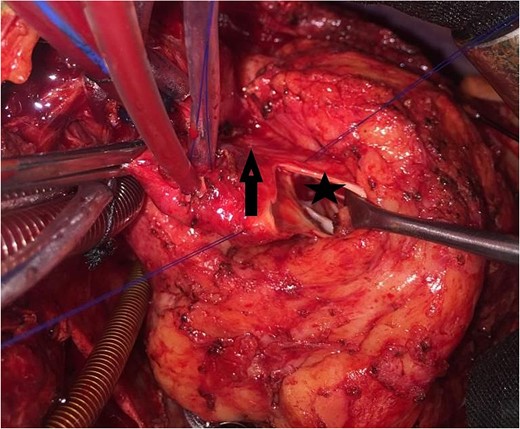

An 11-year-old girl was referred to our hospital with a main complaint of progressive exertional dyspnea. She had undergone surgical repair of SAS 6 years ago. Transthoracic echocardiogram (TTE) revealed the following findings: severe left ventricular hypertrophy, tunnel-like fibromembranous subaortic stenosis with a length of 10 mm, a peak gradient (PG) across the LVOT of 170 mmHg, and mild aortic regurgitation. Based on these findings, the patient was scheduled for elective surgical repair with a possible indication for MKO. The operation was performed via median sternotomy with great caution to avoid inadvertent rupture of any cardiac cavity due to heavy adhesions from the previous operation. The aorta was cannulated just below the takeoff of the innominate artery. Bicaval cannulation was performed to provide a bloodless field. Aortic cross-clamping was applied, and antegrade cold blood cardioplegic solution was administered via a catheter placed in the ascending aorta. The ascending aorta was opened transversely 1 cm above the sinotubular junction (Fig. 1). The aortic valve leaflets were examined carefully to confirm that the aortic valve could be preserved. LVOT was examined thoroughly, and it was clear that the stenosis in the subaortic area was so complex that simple resection through the aortic valve orifice would not be sufficient. The right ventricular outflow tract was opened transversely below the pulmonary valve. The conal papillary muscle was identified (Fig. 2). A right-angle instrument was introduced through the aortic orifice into the interventricular septum, and the tip of the instrument was used to perforate the conal septum to the left of the conal papillary muscle to prevent damage to the conduction system; the septal incision was completed with great caution to avoid damage to the aortic cusps and to extend the incision downward as necessary to completely relieve the stenotic subaortic area (Fig. 3). Interrupted 5/0 Prolene sutures were placed circumferentially around the septal incision to close the interventricular septal defect using a bovine pericardial patch to provide adequate widening of LVOT (Fig. 4). The right ventriculotomy was closed with a second bovine pericardial patch to avoid any possible obstruction of the right ventricular outflow tract (Fig. 5). The remainder of the operation was completed uneventfully. After 6 hours of mechanical ventilation, the patient was extubated, and she convalesced well postoperatively. TTE showed excellent results of the operation with PG across LVOT of 20 mmHg. On 1 year follow-up, the patient was asymptomatic and in very good general condition, and TTE findings confirmed the excellent result.

Intraoperative image showing the bovine pericardial patch used to close the septal incision. (1) Right ventriculotomy and (2) bovine pericardial patch.